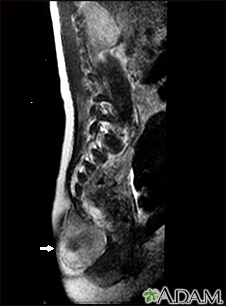

Teratoma - MRI scan